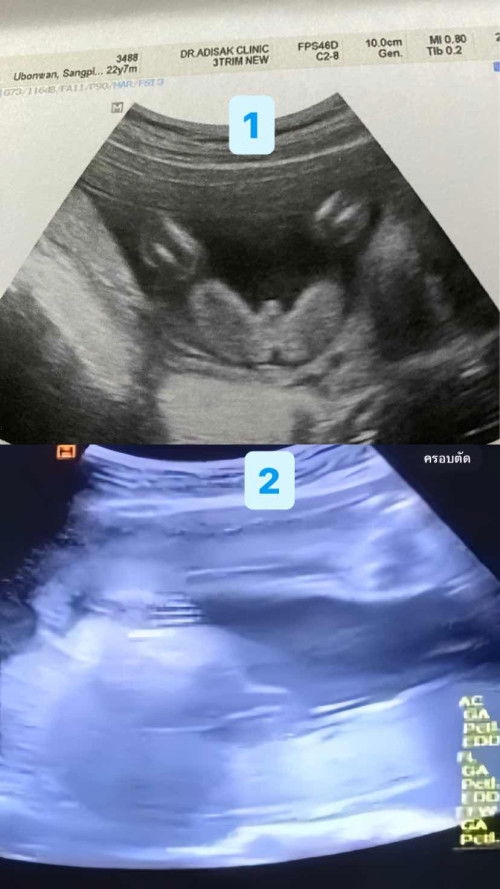

รูปที่1ซาวด์ตอนอายุครรภ์20สัปดาห์หมอบอกว่าผู้ชาย 80% น้องอ้าขาโชว์เห็นชัด แต่หมอก็บอกไม่ชัวส์ รูปที่2ซาว์ล่าสุดอายุครรภ์26สัปดาห์หมอบอกว่าผู้หญิง เห็น3ขีด เปิดรูปที่1ให้หมอดูหมอก็บอกเหมือนผู้ชายแต่ก็ให้ไปลุ้นตอนคลอดอีกที แม่ๆๆพอดูออกไหมคะว่าเพศไหน #ซาวด์อยู่คลีนิคนะคะ